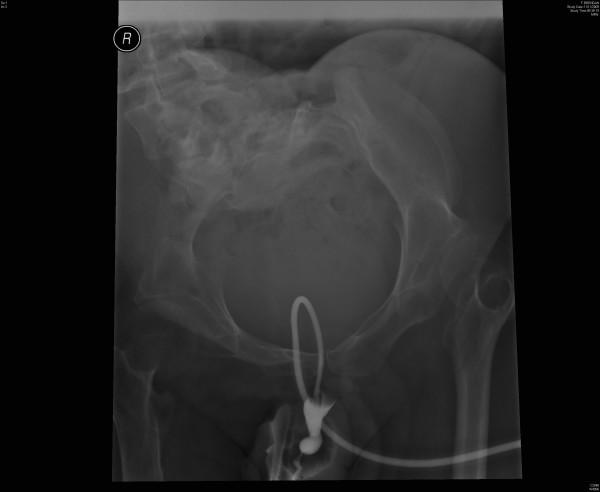

A male patient, born in 1972 with spina bifida and paraplaegia, underwent suprapubic cystostomy in 2003 because of increasing problems with urethral catheter. The patient would come to spinal unit for change of suprapubic catheter every four to six weeks. Two days after a routine catheter change in November 2009, this patient woke up in the morning and noticed that the suprapubic catheter had come out. He went straight to Accident and Emergency. The suprapubic catheter was changed by a health professional and this patient was sent home. But the suprapubic catheter did not drain urine. This patient developed increasing degree of pain and swelling in suprapubic region. He did not pass any urine per urethra. He felt sick and came to spinal unit five hours later. About twenty ml of contrast was injected through suprapubic catheter and X-rays were taken. The suprapubic catheter was patent; the catheter was not blocked. The Foley catheter could be seen going around in a circular manner through the urinary bladder into the urethra. The contrast did not opacify urinary bladder; but proximal urethra was seen. The tip of Foley catheter was lying in proximal urethra. The balloon of Foley catheter had been inflated in urethra. When the balloon of Foley catheter was deflated, this patient developed massive bleeding per urethra. A sterile 22 French Foley catheter was inserted through suprapubic track. The catheter drained bloody urine. He was admitted to spinal unit and received intravenous fluids and meropenem. Haematuria subsided after 48 hours. The patient was discharged home a week later in a stable condition.

一名男性患者,1972年出生,患有脊柱裂及截瘫,2003年因尿道导尿管问题日益增多而接受了耻骨上膀胱造瘘术。该患者每四至六周会到脊髓病治疗单元更换耻骨上导尿管。2009年11月一次常规导尿管更换两天后,该患者早晨醒来发现耻骨上导尿管已脱出。他直接前往急诊。一名医护人员更换了耻骨上导尿管,随后该患者被送回家。但耻骨上导尿管无法引流尿液。该患者耻骨上区域疼痛和肿胀程度不断加重。他尿道未排出任何尿液。他感觉不适,五小时后来到脊髓病治疗单元。通过耻骨上导尿管注入约20毫升造影剂并进行了X光检查。耻骨上导尿管通畅;导管未堵塞。可看到福来导尿管呈环状穿过膀胱进入尿道。造影剂未使膀胱显影;但可见近端尿道。福来导尿管尖端位于近端尿道。福来导尿管的球囊已在尿道内膨胀。当福来导尿管的球囊放气时,该患者尿道出现大量出血。通过耻骨上通道插入一根无菌的22号法国福来导尿管。该导管引出了血尿。他被收入脊髓病治疗单元并接受了静脉补液和美罗培南治疗。48小时后血尿消退。一周后该患者病情稳定出院。